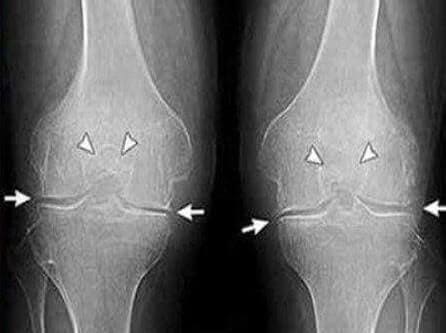

Musiałem iść do lekarza, moja żona nalegała na to. Lekarz rodzinny wysłał mnie do reumatologa, do którego udało mi się dostać w ponad miesiąc, kolejka jednak mocno mnie wymęczyła, w końcu miałem już mocno zniszczone stawy. Przyjął mnie starszy lekarz, bez słowa wysłał na prześwietlenie i badania krwi/moczu. Na drugiej wizycie zdiagnozowano mnie w kilka minut - jakaś artroza, pierwotna czy wtórna, teraz nawet nie pamiętam.

35 dzień: Zrobiłem badania i prześwietlenie. Żadnych śladów artrozy! Chrząstka stawowa jak u 30-letniego faceta. Lekarz powiedział, że na poprzednim RTG najprawdopodobniej był ubytek, więc diagnoza artroza była błędna.